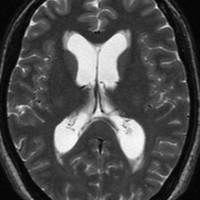

上矢状洞髄膜腫 superior sagittal sinus meningioma

また別な例です。1986年13歳の時に2度の開頭手術を受けましたが,全摘出できずにそのまま経過観察されました。

左の画像は1997年の術前のものです。これを2回に分けて全摘出しました。上矢状洞はやはり冠状縫合のあたりから静脈洞交会まで摘出しました。その下の大脳鎌も全て摘出したので,直静脈洞の上壁を開けることになり,直静脈洞からの激しい出血があり縫合して直静脈洞形成をするのが大変でした。手術後16年が経過しますが再発していませんし,社会人として普通に暮らせています。

この例が教えてくれることは,上矢状静脈洞は全長にわたり切除してしまっても,神経脱落症状を出さないで普通に生きて行かれるということです。